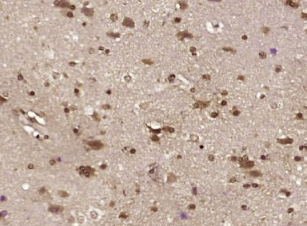

多聚甲醛固定,石蜡包埋(人脑胶质瘤);用柠檬酸钠缓冲液煮沸(15分钟)提取抗原;用3%过氧化氢阻断内源性过氧化物20分钟;阻断缓冲液(正常山羊血清)37℃30分钟;抗体孵育(Ⅱ)。未结合的环抗体在1:400下在4°C下过夜,然后根据SP试剂盒(兔子)说明和DAB染色进行操作。